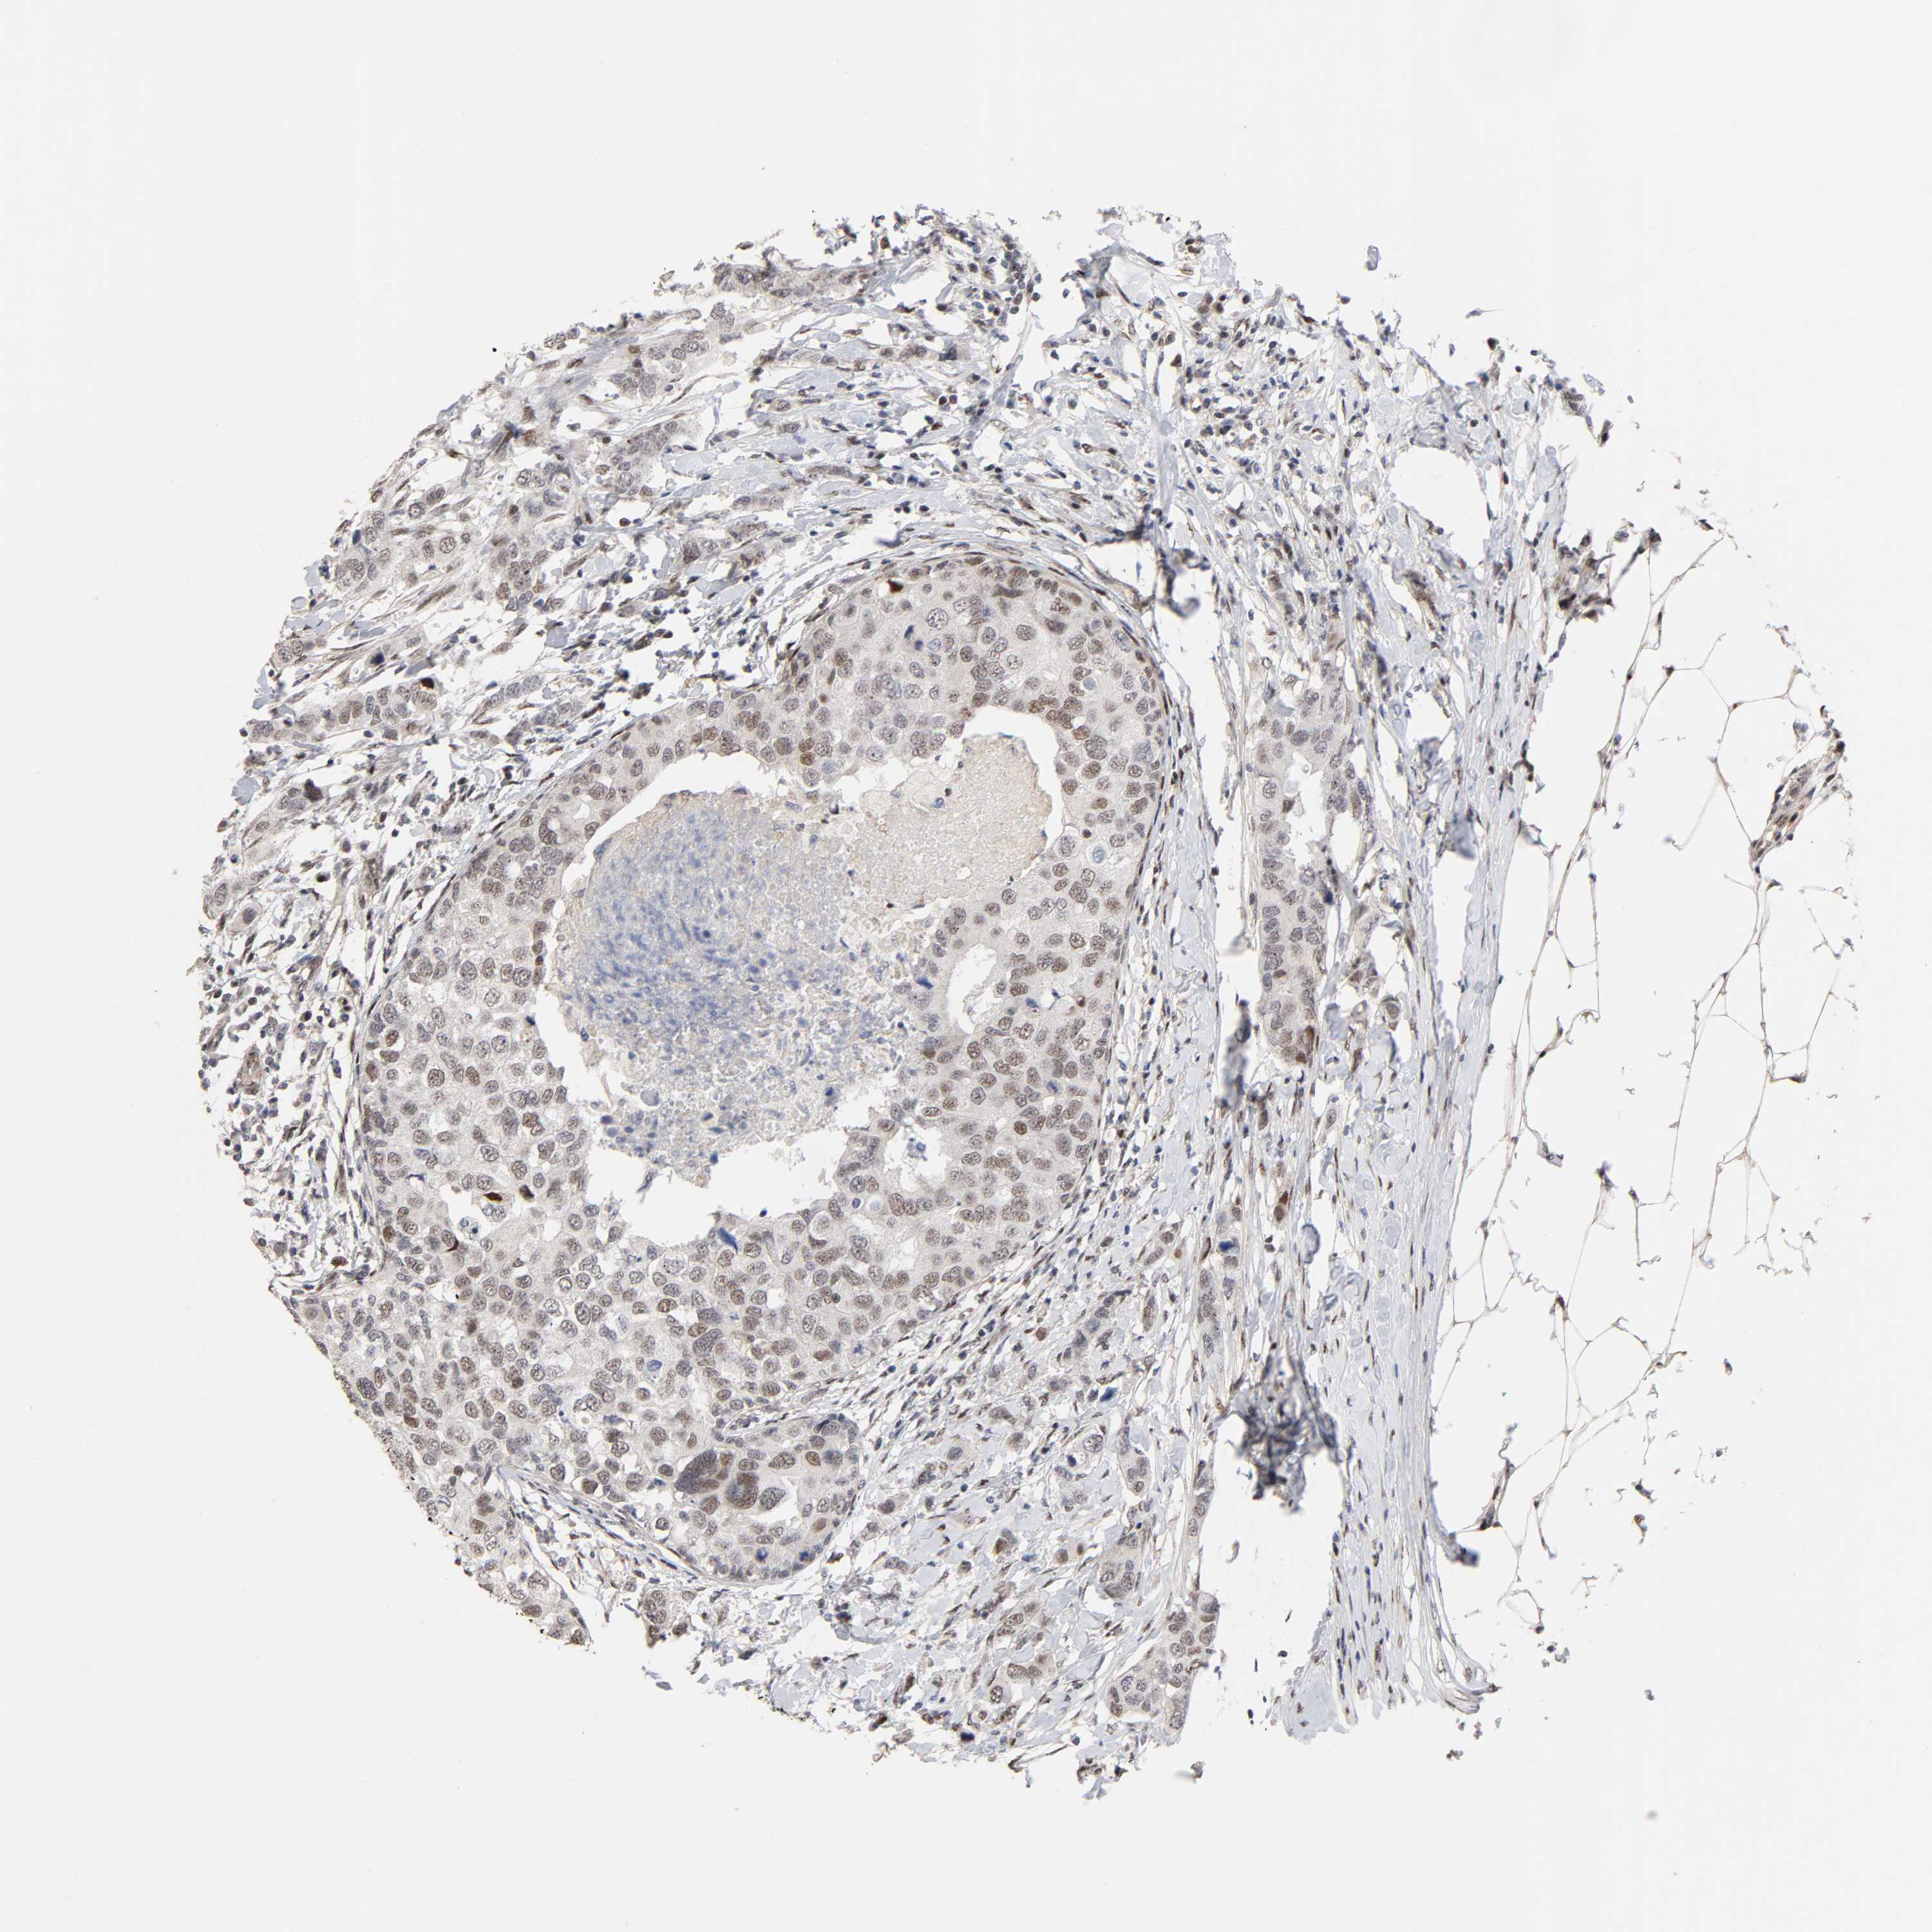

BRCA TCGA BRCA VALIDATION PROTEIN EXPRESSION

ANTIBODIES

AND

VALIDATION